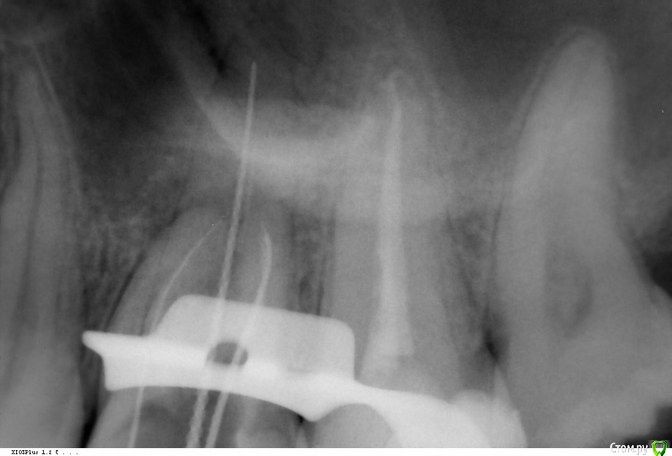

Викторри Опубликовано 16 февраля, 2018 Поделиться Опубликовано 16 февраля, 2018 Здравствуйте,уважаемые доктора и пациенты! Проблема 26 зуб, лечение по поводу пульпита в 2011г (если необходимо, могу прикрепить снимок).В ноябре 2017г обнаружена киста ,проявлявшаяся реакцией на горячее. В декабре 2017 за 3 сеасна открыты 3 и пройден 4 канал. В наст время готовлюсь к постоянной пломбировке (в каналах каласепт уже 8 недель). Меня смущает картина прохождения канала (вроде дистальный),к-ый самый длинный, а именно кажется,что не прошли его до верхушки.Вопросы :1. права ли я на счет не до конца пломбир. канала?Если да-что делать?2. необходимо ли нахождение Каалсепта такое длительное время в каналах? Очень жду ответа.Спасибо Ссылка на комментарий

red_butler Опубликовано 16 февраля, 2018 Поделиться Опубликовано 16 февраля, 2018 1. права ли я на счет не до конца пломбир. канала? нет Если да-что делать? Вы не доверяете своему врачу? Ссылка на комментарий

Викторри Опубликовано 16 февраля, 2018 Автор Поделиться Опубликовано 16 февраля, 2018 нет Вы не доверяете своему врачу?Здравствуйте,спасибо за ответ. Т.е. канал пройден до верхушки? На счет 2-го ?: ситуация след: этот доктор не мой постоянный (мой в другом городе), я пытаюсь ей верить, но я вот из-за такой же кисты уже потеряла 36 зуб и 26 перелечиваю из-за пропущенного и недолеченных каналов. Обжегшись на молоке - на воду дуешь Ссылка на комментарий

red_butler Опубликовано 16 февраля, 2018 Поделиться Опубликовано 16 февраля, 2018 Т.е. канал пройден до верхушки? да На счет 2-го ? стандартных сроков нет, переходите к постоянному пломбированию но я вот из-за такой же кисты уже потеряла 36 зуб все будет хорошо 1 Ссылка на комментарий